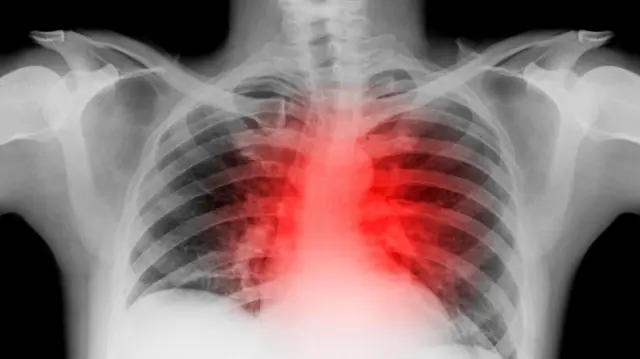

ਤਸਵੀਰ ਸਰੋਤ, Getty Images

ਡਾਕਟਰਾਂ ਦੀ ਮੰਨੀਏ ਤਾਂ ਦਿਲ ਦੇ ਦੌਰੇ ਦਾ ਵੱਡਾ ਲੱਛਣ ਹੈ- ਛਾਤੀ ਵਿੱਚ ਦਰਦ। ਦਰਦ ਕਰਕੇ ਸਾਡੀਆਂ ਅੱਖਾਂ ਵਿੱਚ ਘਬਰਾਹਟ ਦਿਸਣ ਲੱਗਦੀ ਹੈ ਅਤੇ ਮਰੀਜ਼ ਥੱਲੇ ਡਿੱਗ ਜਾਂਦਾ ਹੈ, ਇੰਝ ਲਗਦਾ ਹੈ ਜਿਵੇਂ ਸਾਡਾ ਦਿਲ ਕੁਚਲਿਆ ਜਾ ਰਿਹਾ ਹੋਵੋ ਪਰ ਜ਼ਰੂਰੀ ਨਹੀਂ ਹਰ ਵਾਰ ਇਹ ਮਹਿਸੂਸ ਹੋਵੇ।

ਜਦੋਂ ਦਿਲ ਤੱਕ ਲੋੜੀਂਦਾ ਖੂਨ ਨਹੀਂ ਪਹੁੰਚਦਾ ਤਾਂ ਦਿਲ ਦਾ ਦੌਰਾ ਪੈਂਦਾ ਹੈ। ਅਕਸਰ ਧਮਣੀਆਂ ਦੀ ਰੁਕਾਵਟ ਕਰਕੇ ਖ਼ੂਨ ਦੇ ਦਿਲ ਤੱਕ ਪਹੁੰਚਣ ਵਿੱਚ ਮੁਸ਼ਕਿਲ ਹੁੰਦੀ ਹੈ, ਇਸੇ ਕਰਕੇ ਦਰਦ ਹੁੰਦਾ ਹੈ। ਕਦੇ-ਕਦੇ ਬਿਨਾਂ ਦਰਦ ਦੇ ਵੀ ਦੌਰਾ ਪੈ ਜਾਂਦਾ ਹੈ ਜਿਸ ਨੂੰ ਸਾਈਲੈਂਟ ਅਟੈਕ ਜਾਂ ਖਾਮੋਸ਼ ਦੌਰਾ ਕਿਹਾ ਜਾਂਦਾ ਹੈ।